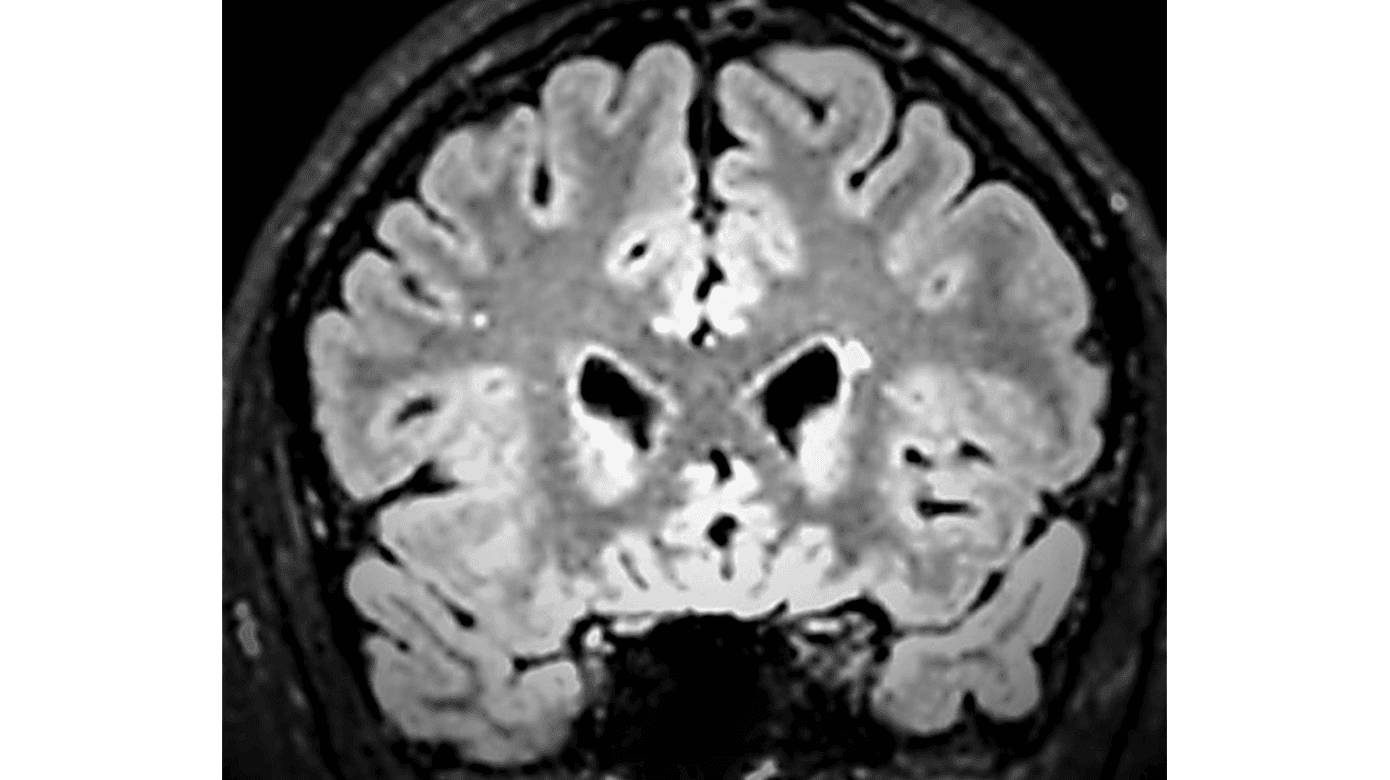

En 27-årig mand, tidligere rask, blev henvist i november 2021 på grund af tiltagende hovedpine. Han relaterede hovedpinen til et mindre hovedtraume under boldspil i juli 2021. Ved anamneseoptagelsen fremgik det dog, at hovedpinen opstod en uge efter hovedtraumet, som ikke var forbundet med bevidsthedspåvirkning. Samtidig kom det frem, at patienten havde deltaget i et overlevelseskursus en måned før, men han huskede ikke at have observeret hudforandringer. Han oplevede dobbeltsyn ved blik ligefrem, havde intermitterende svimmelhed, vedvarende lysfølsomhed og paræstesier i fingrene samt generelt nedsat energiniveau. Undersøgelserne viste latent udadskelen og indskrænket indaddrejning af øjnene. MR-skanning af cerebrum i april 2022 viste jukstakortikale og periventrikulære læsioner (Figur 1).

På mistanke om MS blev der foretaget spinalvæskeundersøgelse i maj 2022, som viste otte mononukleære celler, forhøjet IgG-indeks og oligoklonale bånd. Endelig fandtes positivt, intratekalt Borrelia-antistofindeks. Patienten startede behandling med doxycyclin 200 mg dagligt i tre uger. Ved opfølgning efter 12 måneder anførte han betydelig bedring af hovedpinen og tydelig mindskning af lysoverfølsomheden, men fortsat påvirkning af livskvaliteten, da han ofte måtte selektere i, hvad han kunne overkomme. Hukommelsen var god, men der var fortsat koncentrationsbesvær. Øjenlægeundersøgelse i juni 2023 viste helt normale forhold. Kontrol-MR-skanninger viste uændrede forhold i september 2022 og i september 2023.